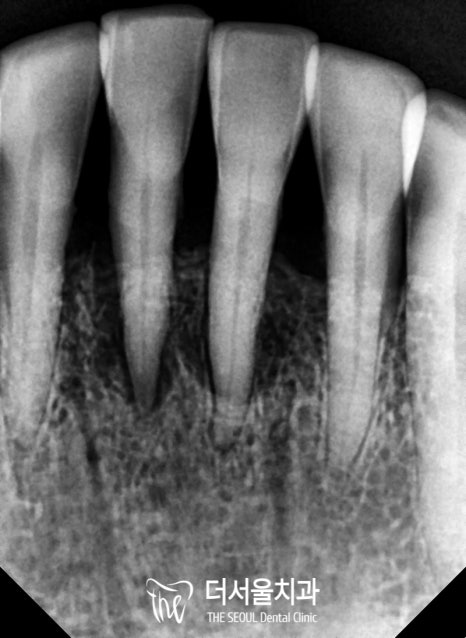

이전에는 잇몸이 내려앉고

안에 있는 조직이 드러나서

심미성이 떨어질 수 밖에 없었는데요.

실제 자연치와 유사한

지르코니아를 사용하여

좀 더 건강한 치아를 만들어주었습니다.

앞니임플란트 와 더불어 아래 쪽의 브릿지도

심미성은 물론이며 컨택, 교합이 잘 맞게끔

제작이 된 것이 관찰되네요.